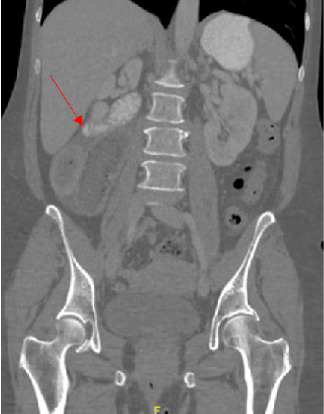

Abstract Image